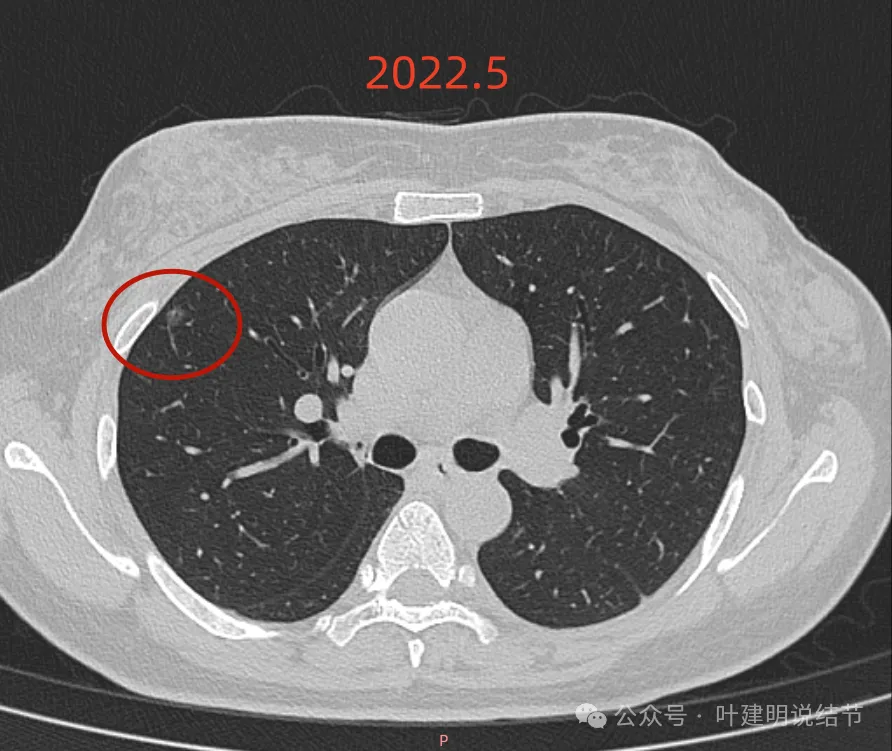

再看2022年5月时的影像:

这时B医院医生主张手术时的情况:

三处病灶均仍在,间隔3个月显然说不上明显进展或变化。这时候问诊我,我对比后认为风险仍低,能再随访,结友停掉了本已经预约的手术。